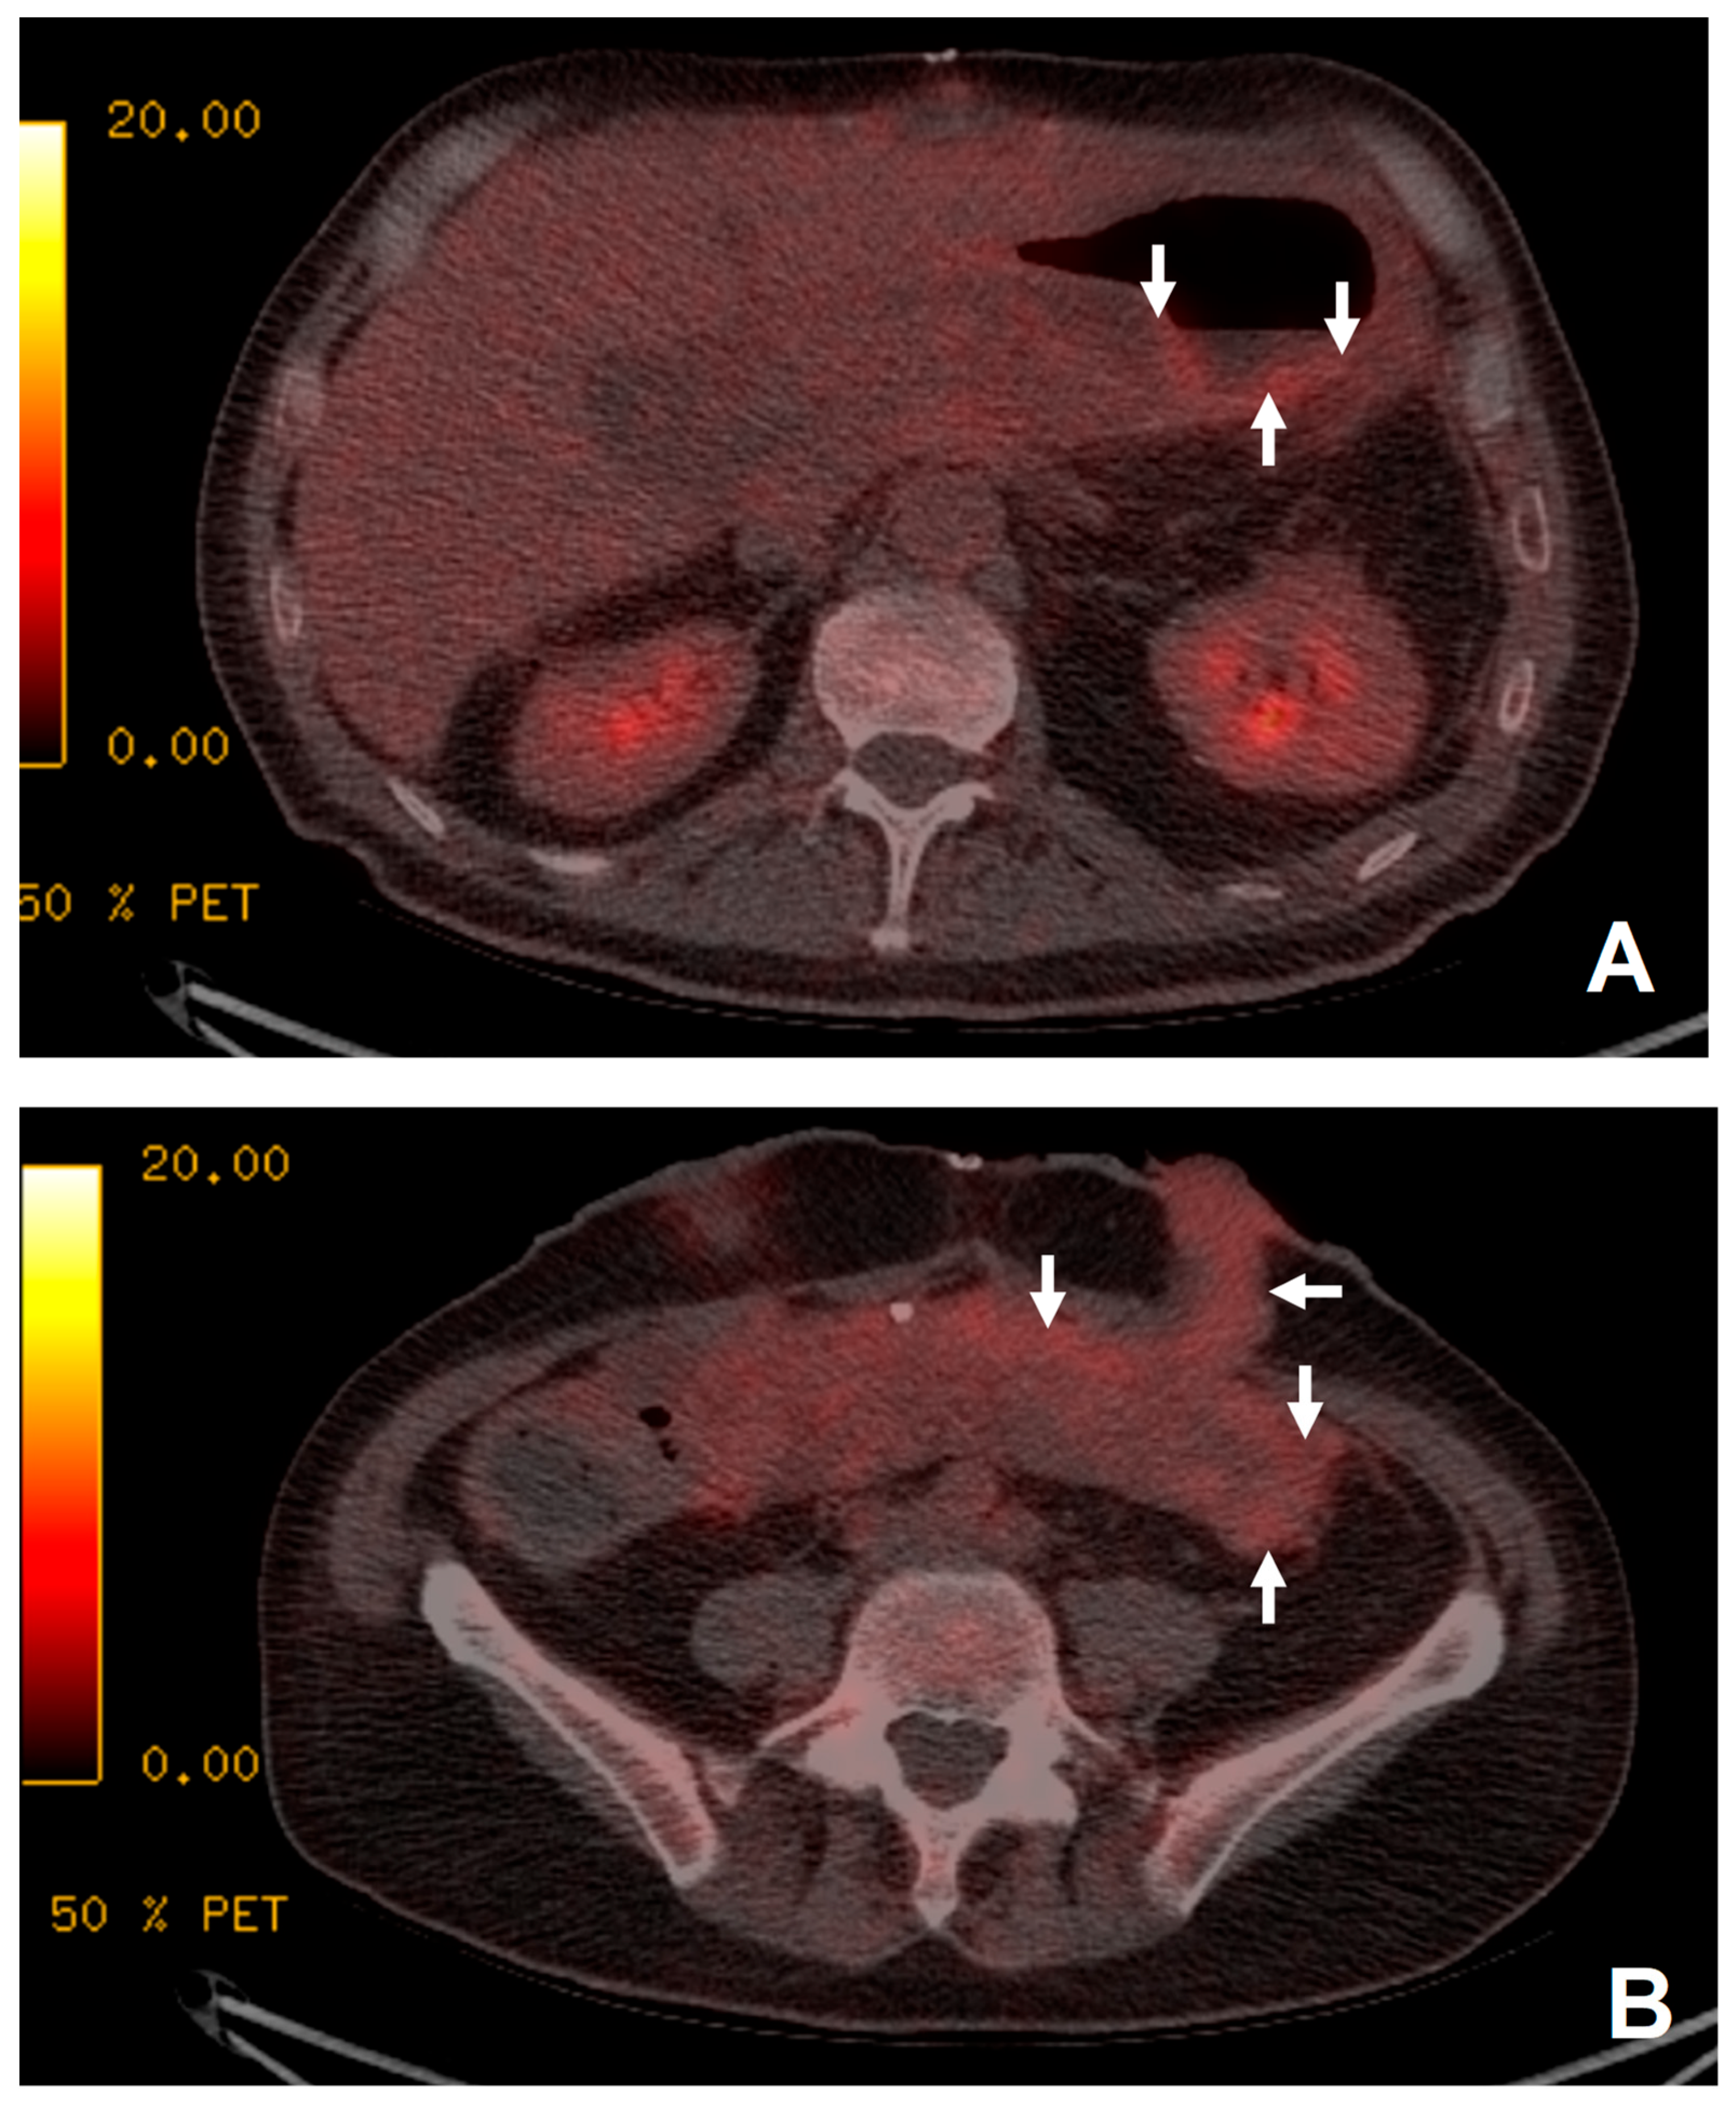

Figure 2. The patient presented with 1 week of pyrexia but no source of infection was identified. Increased uptake was demonstrated in the transplanted stomach (white arrows, image (A)) and small bowel (white arrows, image (B)) suggestive of rejection. Biopsy just prior to 18F-FDG PET/CT demonstrated a non-specific increase in apoptotic debris within the lamina propria of uncertain significance. As no focus of infection was demonstrated and the appearance of the transplanted stomach (A) and small bowel (B) was suggestive of rejection, the patient was treated for rejection with immune suppression. Following anti-rejection treatment, the patient’s clinical picture improved with resolution of the pyrexia. Subsequent biopsies taken 6 weeks later demonstrated no remaining features of rejection.

There were 17 examinations that could answer the clinical question regarding the possibility and the source of sepsis. Among these, seven of the examinations localized the source of sepsis (Figure 1). Of these, 10 examinations were able to exclude the presence of a source of sepsis to account for the patient’s symptoms, but incidental findings of rejection were noted in two patients (Figure 2) and myositis in one patient. The remaining examination was deemed unhelpful by the referring clinical team.

In one patient with suspected sepsis, rejection was suggested on the 18F-FDG PET/CT and this was confirmed on biopsy (Figure 2).